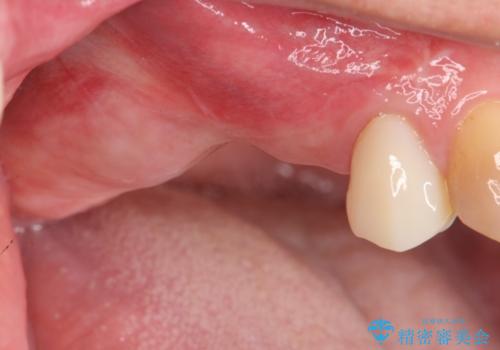

骨の造成を伴う奥歯のインプラント治療

- 破折した歯を放置し、骨が高度に吸収した状態でインプラント治療を希望し来院されました。

インプラントを適切な位置に埋入し仕上げた後にも清掃性を高めるには、必要十分な骨となだらかな歯肉形態の獲得が必要です。

インプラント埋入時に骨の造成を、2次手術時に歯肉の凹みを整え厚みを一定にするような治療を進めていきます。

骨の造成、歯肉を整えたことで、術前山形にえぐれていた歯肉形の態はなだらかになり清掃しやすい状態へと整備することができました。